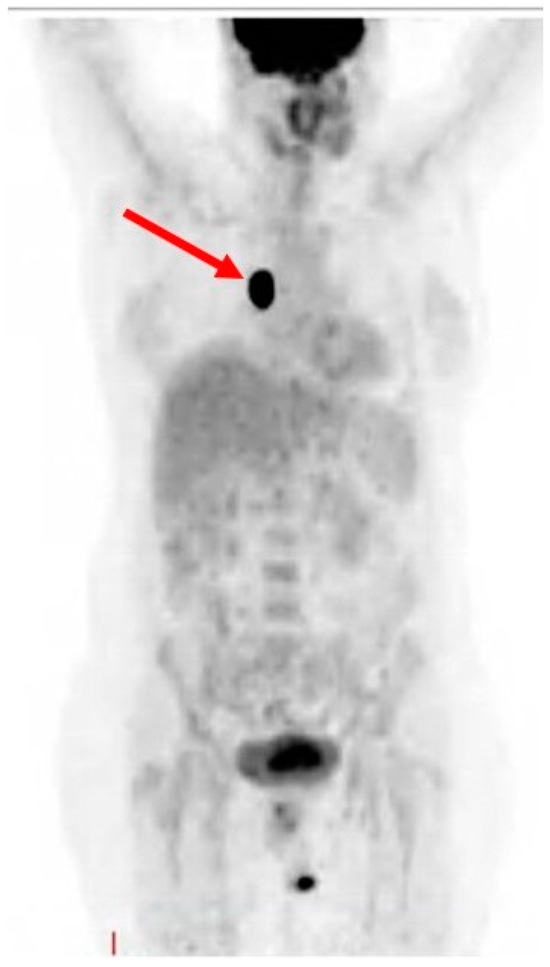

As of August 2023, the patient had received 41 cycles of therapy without adverse effects incidents and a recent PET–CT scan showed a complete response to treatment (Figure 4).

Figure 4. PET–CT scan showing no evidence of disease.